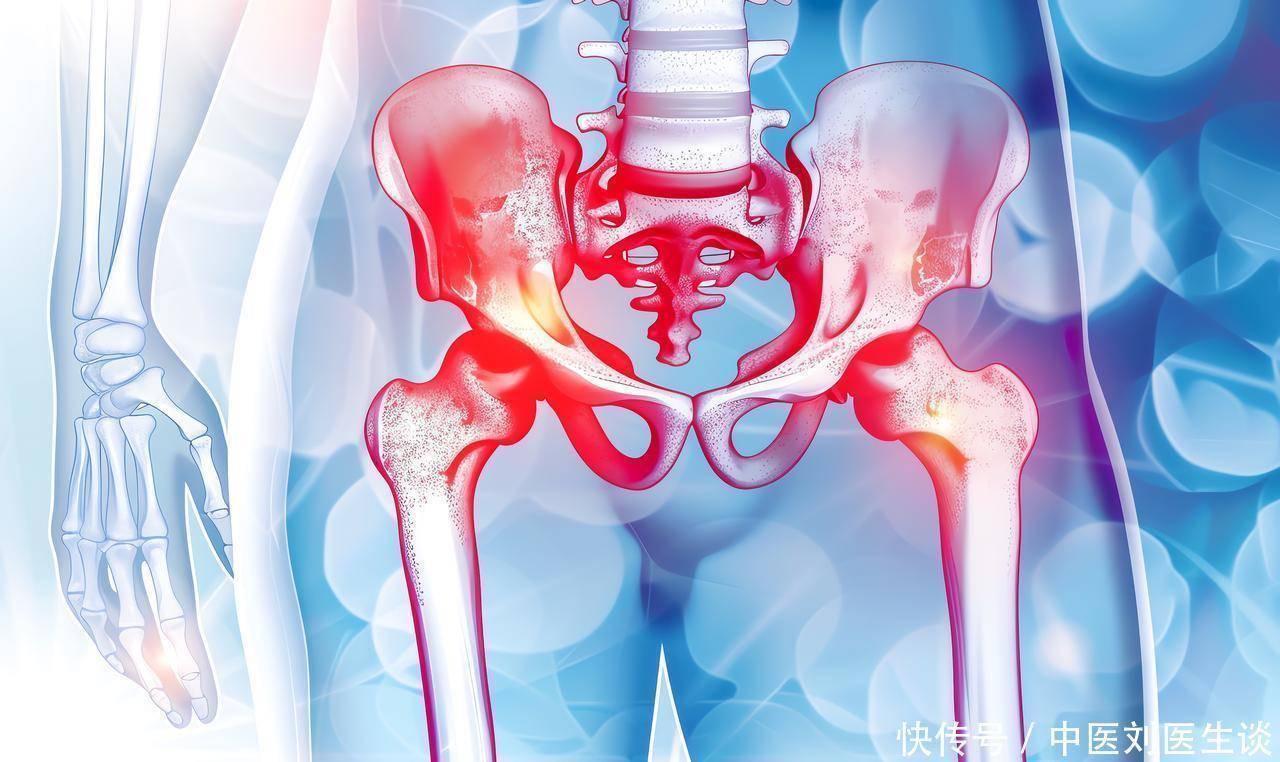

站立有点费劲,上下楼梯像在爬山,转身时“咯噔”一下的麻痒感,这些都是髋关节在悄悄“抗议”。不少朋友忍着,觉得“人老了都这样”,或者小心翼翼地问医生:“我这痛到底是骨头问题、软骨磨损千红网,还是筋腱卡住了?”那种上医院跑了好几趟,检查单子看完一堆,可医生还是含糊其辞,让你先试试这个药、再试试那个理疗,结果效果甚微的迷茫感,真的让人心力交瘁。